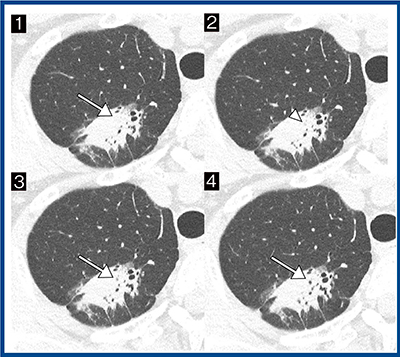

代表例を提示する(図5)。症例は,50歳代,女性,浸潤性肺腺癌(浸潤部2.5cm)である。3.1cm大の部分充実結節は,超高精細CTにて形態が不整な細気管支透亮像を認め,一部で途絶も確認された(図5→,▶)。途絶直前の径は約1.3mmであった。

図5 最高分解能の画像による細気管支の途絶の評価(浸潤性肺腺癌)

(1→4の順で頭側→尾側)